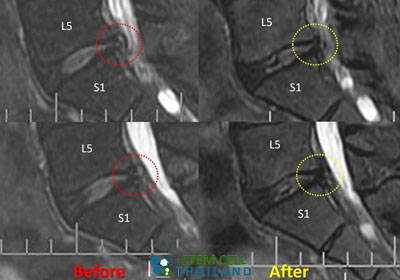

Treatment for Desiccated Discs & DiscopathyDDD-Before-After-treatment-MRI

When the discomfort and pain from degenerative spine & degenerative disc disease are severe, conventional operative therapies are often ineffective. For these inoperative conditions, adult autologous stem cells can offer an innovative non-surgical therapeutic method to reverse bulging disc degeneration and address the chronic low back pain at its root. Chronic lower back pain due to degenerative disc illness impacts an estimated 17 million individuals worldwide. While short-term solutions can be achieved by the use of analgesics, steroids, having enough rest and frequent physiotherapy, there are still many people diagnosed with discopathy whose conditions rapidly become worse despite the traditional treatments that were recommended by the orthopedic surgeons.

before-after-mri-stem-cells-sports-injuries-prp-Orthokine-regenokineThe Regeneration Center recommends a unique approach to dealing with a degenerating back. With enhanced mesenchymal stem cells, post-therapy rehab and joint pain friendly diet plan, (MSC+) cells for neurological & spinal conditions can be used to repair the degenerative state of the spinal disks and surrounding tissue. We offer Autologous and Allogeneic stem cell therapies using CD34+ stem cells is safe and effective for those with advanced degenerative disc disease and severe back pain due to failed surgeries or spinal arthritis. Our center uses isolated and expanded MSC+ cells that have immunomodulatory properties and decrease the damage of tissue by immune cells. These MSC+ cells take advantage or the paracrine cell signaling mechanism to secrete neuroprotective factors and recruit angiogenic properties that help to restore the damaged areas of the spinal cord and also help to increase blood supply to surrounding tissues. [2] Patients with severe degeneration, peripheral neuropathy or multiple ailments including strokes, ataxia or artery disease may require a combination therapy using a combination of stem cells from Umbilical Cord Tissue or Placenta-derived stem cells. Patients undergoing disc regeneration for DDD can expect minimal discomfort with safe cell isolation methods and delivery systems. Improvements are noticed pretty quickly after the first treatment starting with a reduction in pain while the body starts going through its natural regenerative cycle. [3] .